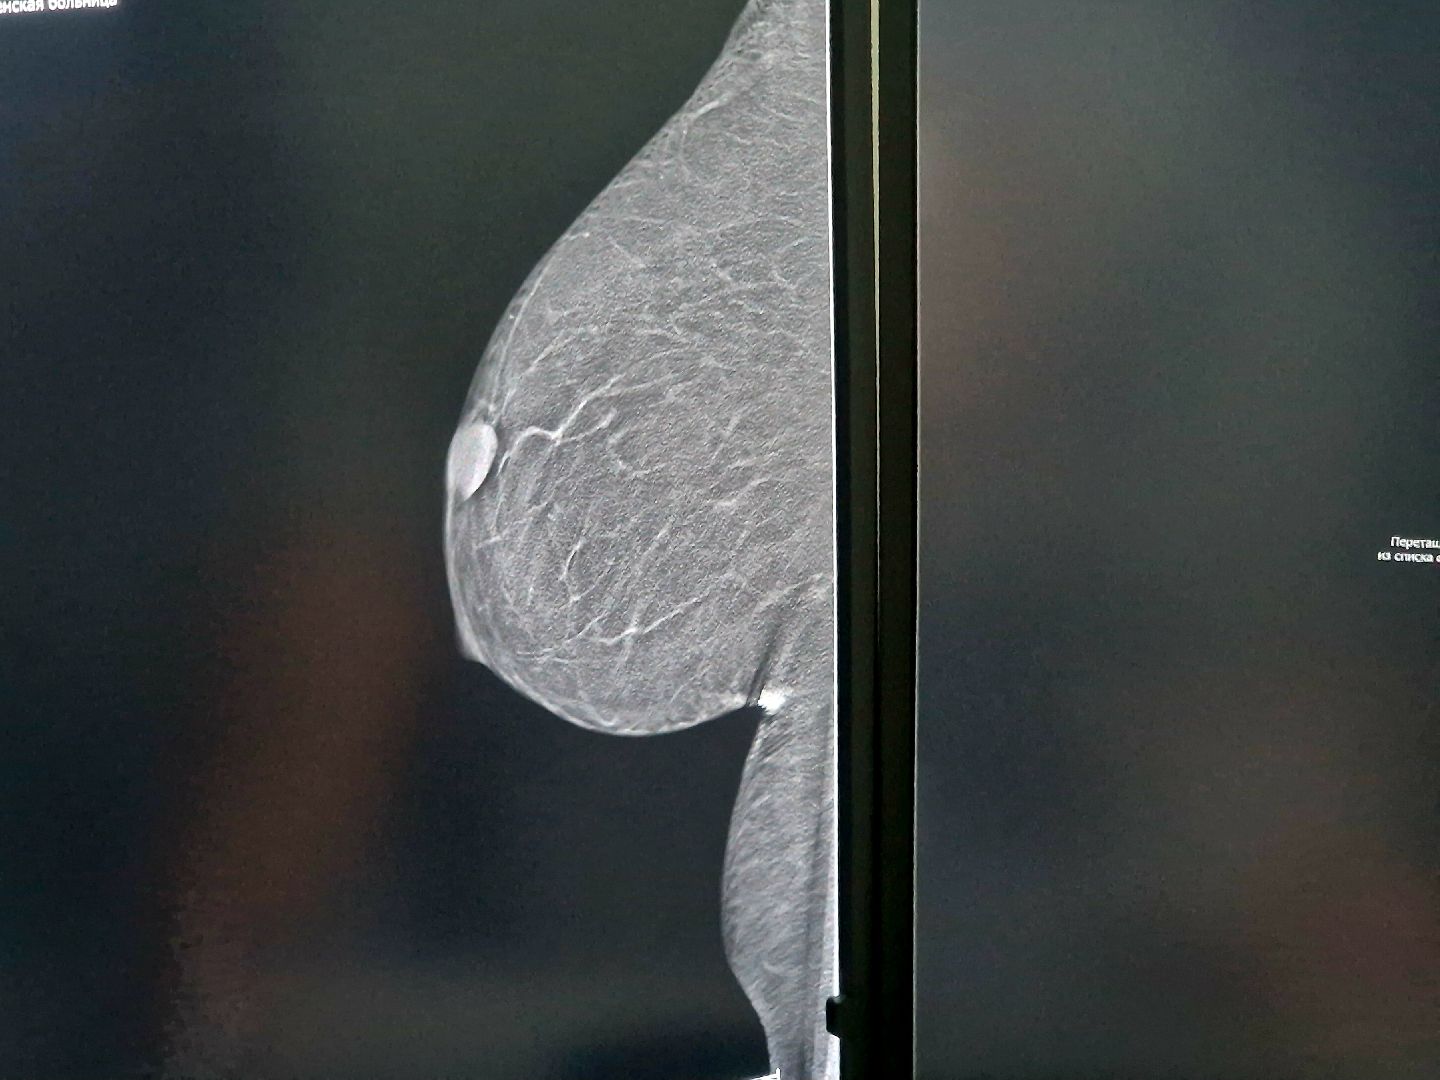

В Воскресенском Центре здоровья начал работать новый маммограф «Маммо-5МТ». Отечественный аппарат помогает улучшить диагностику заболеваний молочной железы на ранних стадиях.

Врач-рентгенолог Ирина Шлыкова сообщила, что обследования проводятся ежедневно, с 8:00 утра до 17:00. По её словам, маммография чаще всего позволяет увидеть образования размером от одного сантиметра. Новый маммограф оснащён сенсорной панелью. Аппарат делает снимки под углом 45 градусов, что обеспечивает высокую точность и является залогом надёжной диагностики.

Одно из главных преимуществ нового современного аппарата – функция томосинтеза. Врач объяснила, что это возможность делать множество снимков-срезов одной молочной железы. Бывает, что на обычном снимке опухоль не видно, но её можно разглядеть на отдельных срезах. Если врачи обнаруживают образование, то следующим шагом становится пункция, чтобы определить, из каких клеток оно состоит и есть ли среди них раковые.